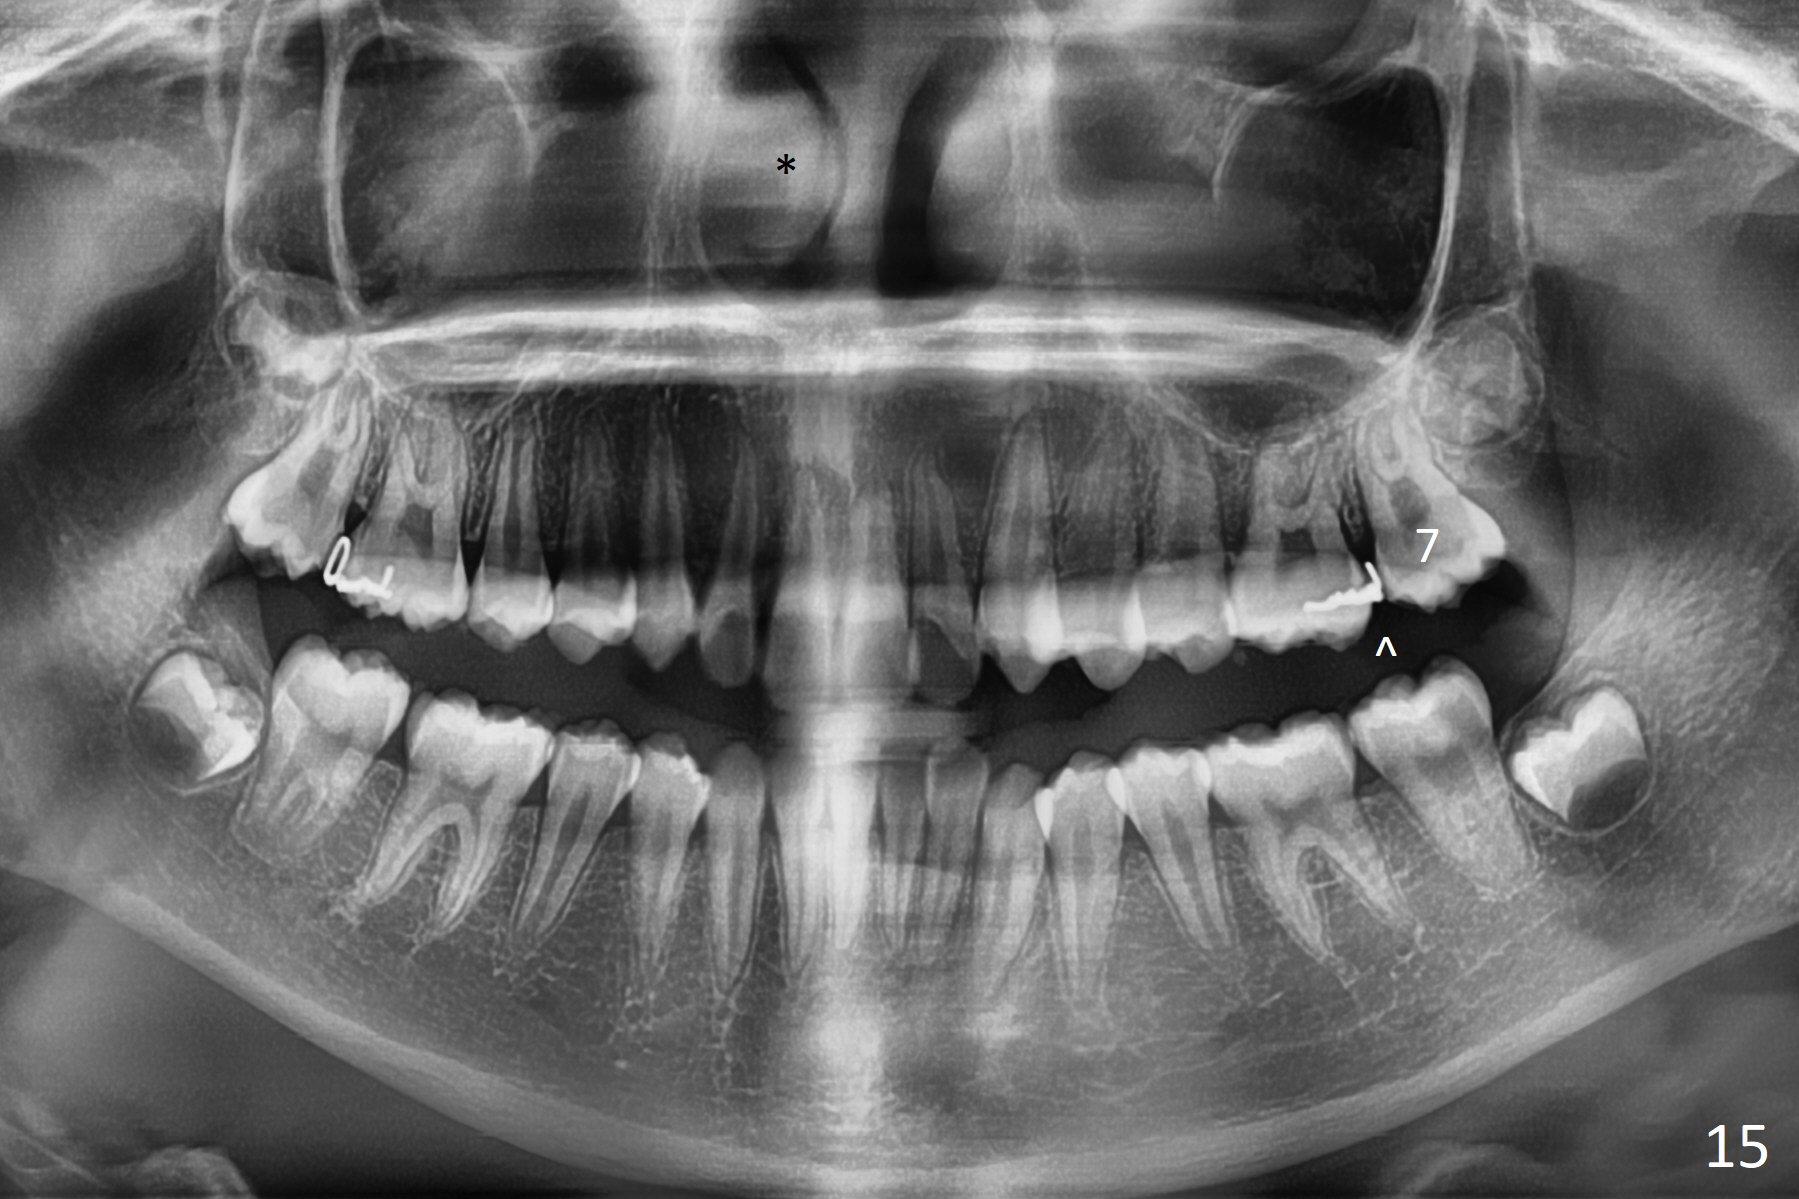

A 12-year-old woman has normal facial profile (Fig.1-6,12) and crowded dentition (7-11). Because of erupting 2nd molars (Fig.10,15), it is difficult to place rubber separators between U6/7. Copper ones are used instead (Fig.15 ^). Crowding and narrow arches (Fig.13,14) may be associated with the enlarged right Inferior Nasal Concha (Fig.15 *).